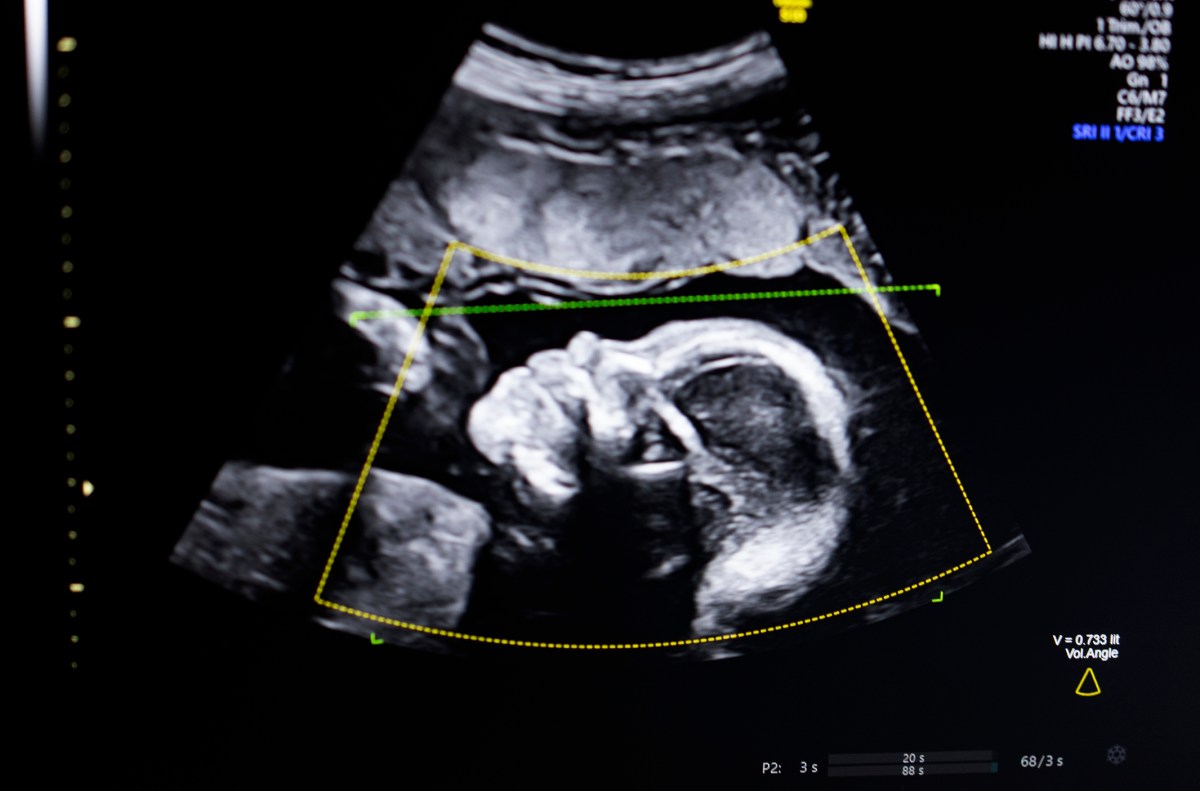

The technology uses computer vision AI to “support fetal ultrasound quality assessment, anatomical completeness, automated reporting, and seamless integration into clinical workflow,” Bustami told TechCrunch.

Bastami said that prenatal ultrasound has become a “cornerstone” in monitoring pregnancies, but its low-quality images can lead to incorrect diagnosis.

Bustami said the hardest part was not building its AI models, which were trained on a variety of 11,000 ultrasound images, but ensuring the technology performed reliably in the real world, especially with the demographics most at risk of a tragic outcome.